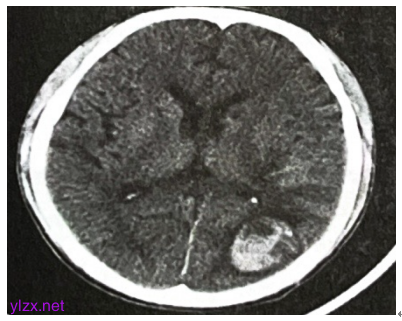

双侧髂静脉、股静脉、胭静脉、胫前静脉及胫后静脉未见明显异常。颅脑CT:左侧枕叶出血,左顶叶小灶性出血可能(图3)。

图3 颅脑CT